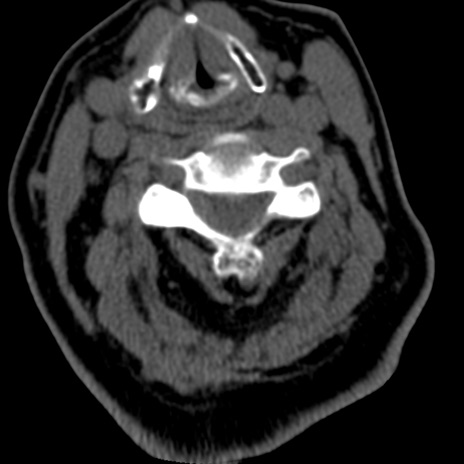

症例50 頚椎CT(横断像)

矢状断像